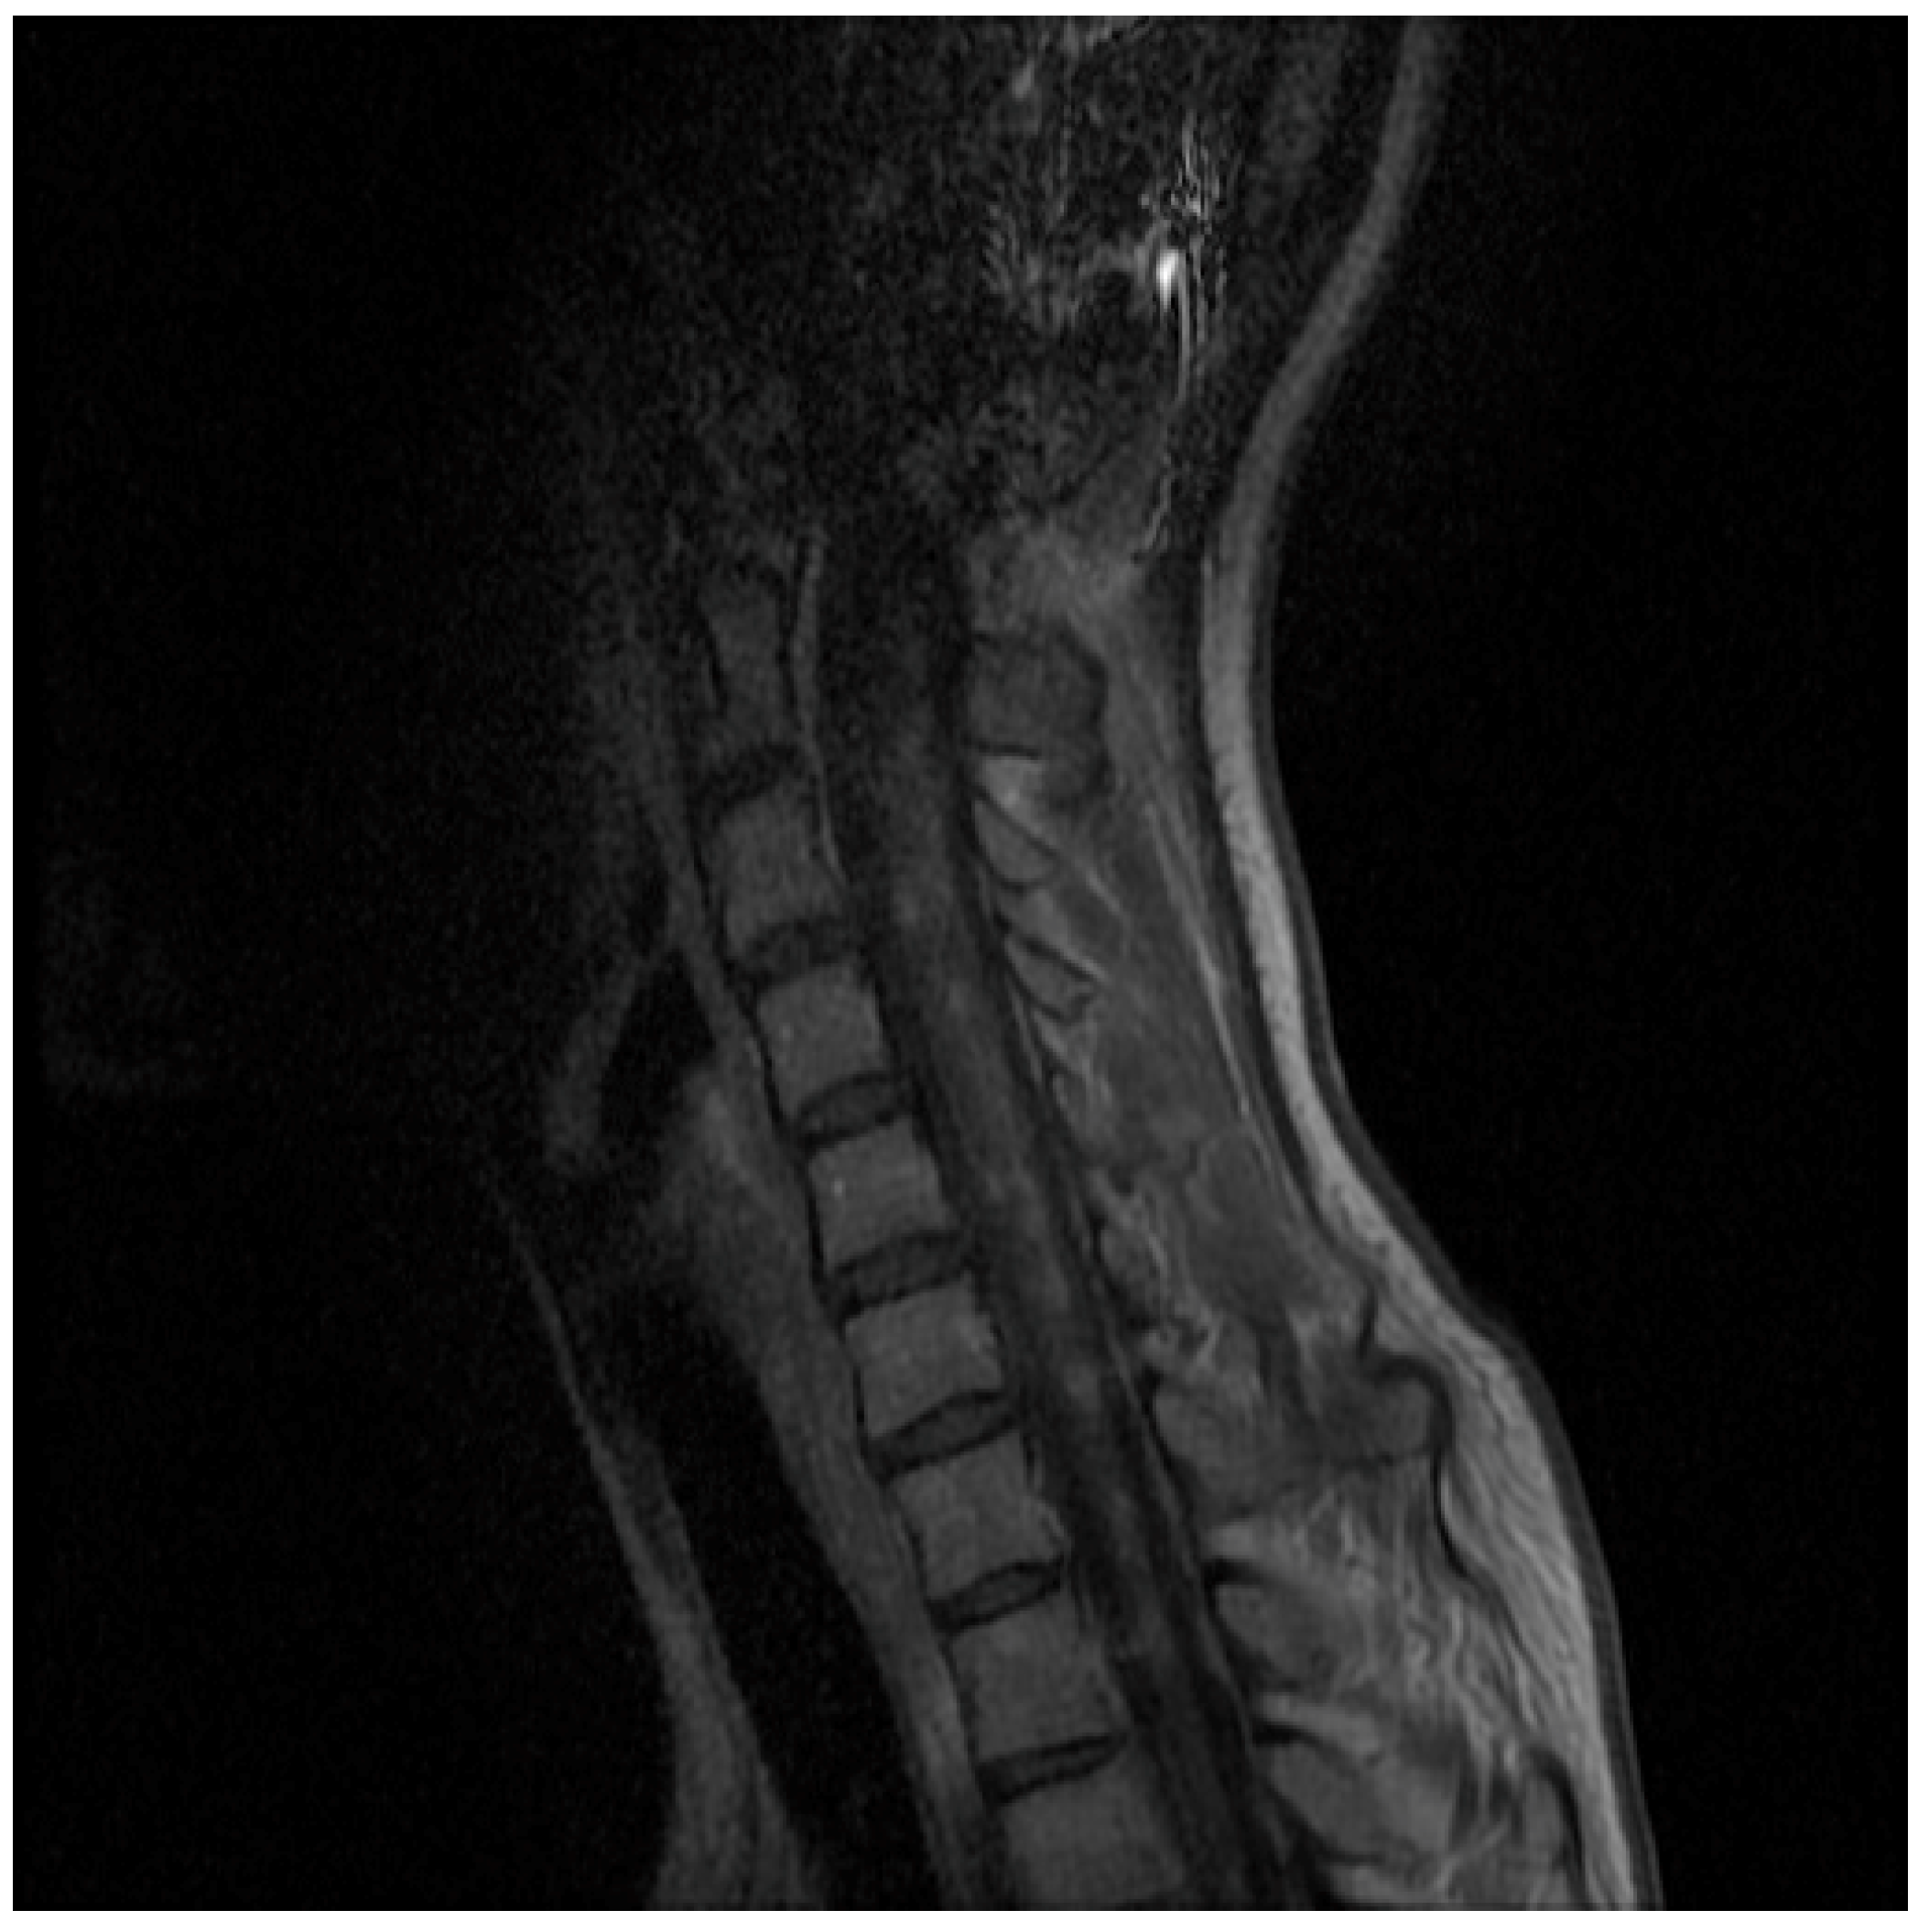

2. Case Presentation